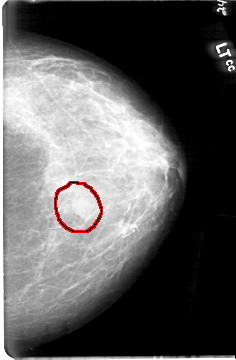

FILE: D_4092_1.LEFT_CC.OVERLAY

TOTAL_ABNORMALITIES 1

ABNORMALITY 1

LESION_TYPE MASS SHAPE OVAL MARGINS OBSCURED

ASSESSMENT 0

SUBTLETY 4

PATHOLOGY BENIGN

TOTAL_OUTLINES 1

BOUNDARY